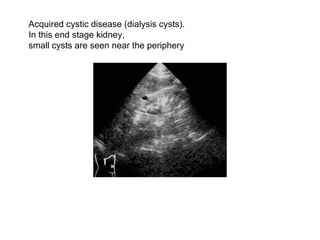

Acquired cystic disease (dialysis cysts).  In this end stage kidney,  small cysts are seen near the periphery